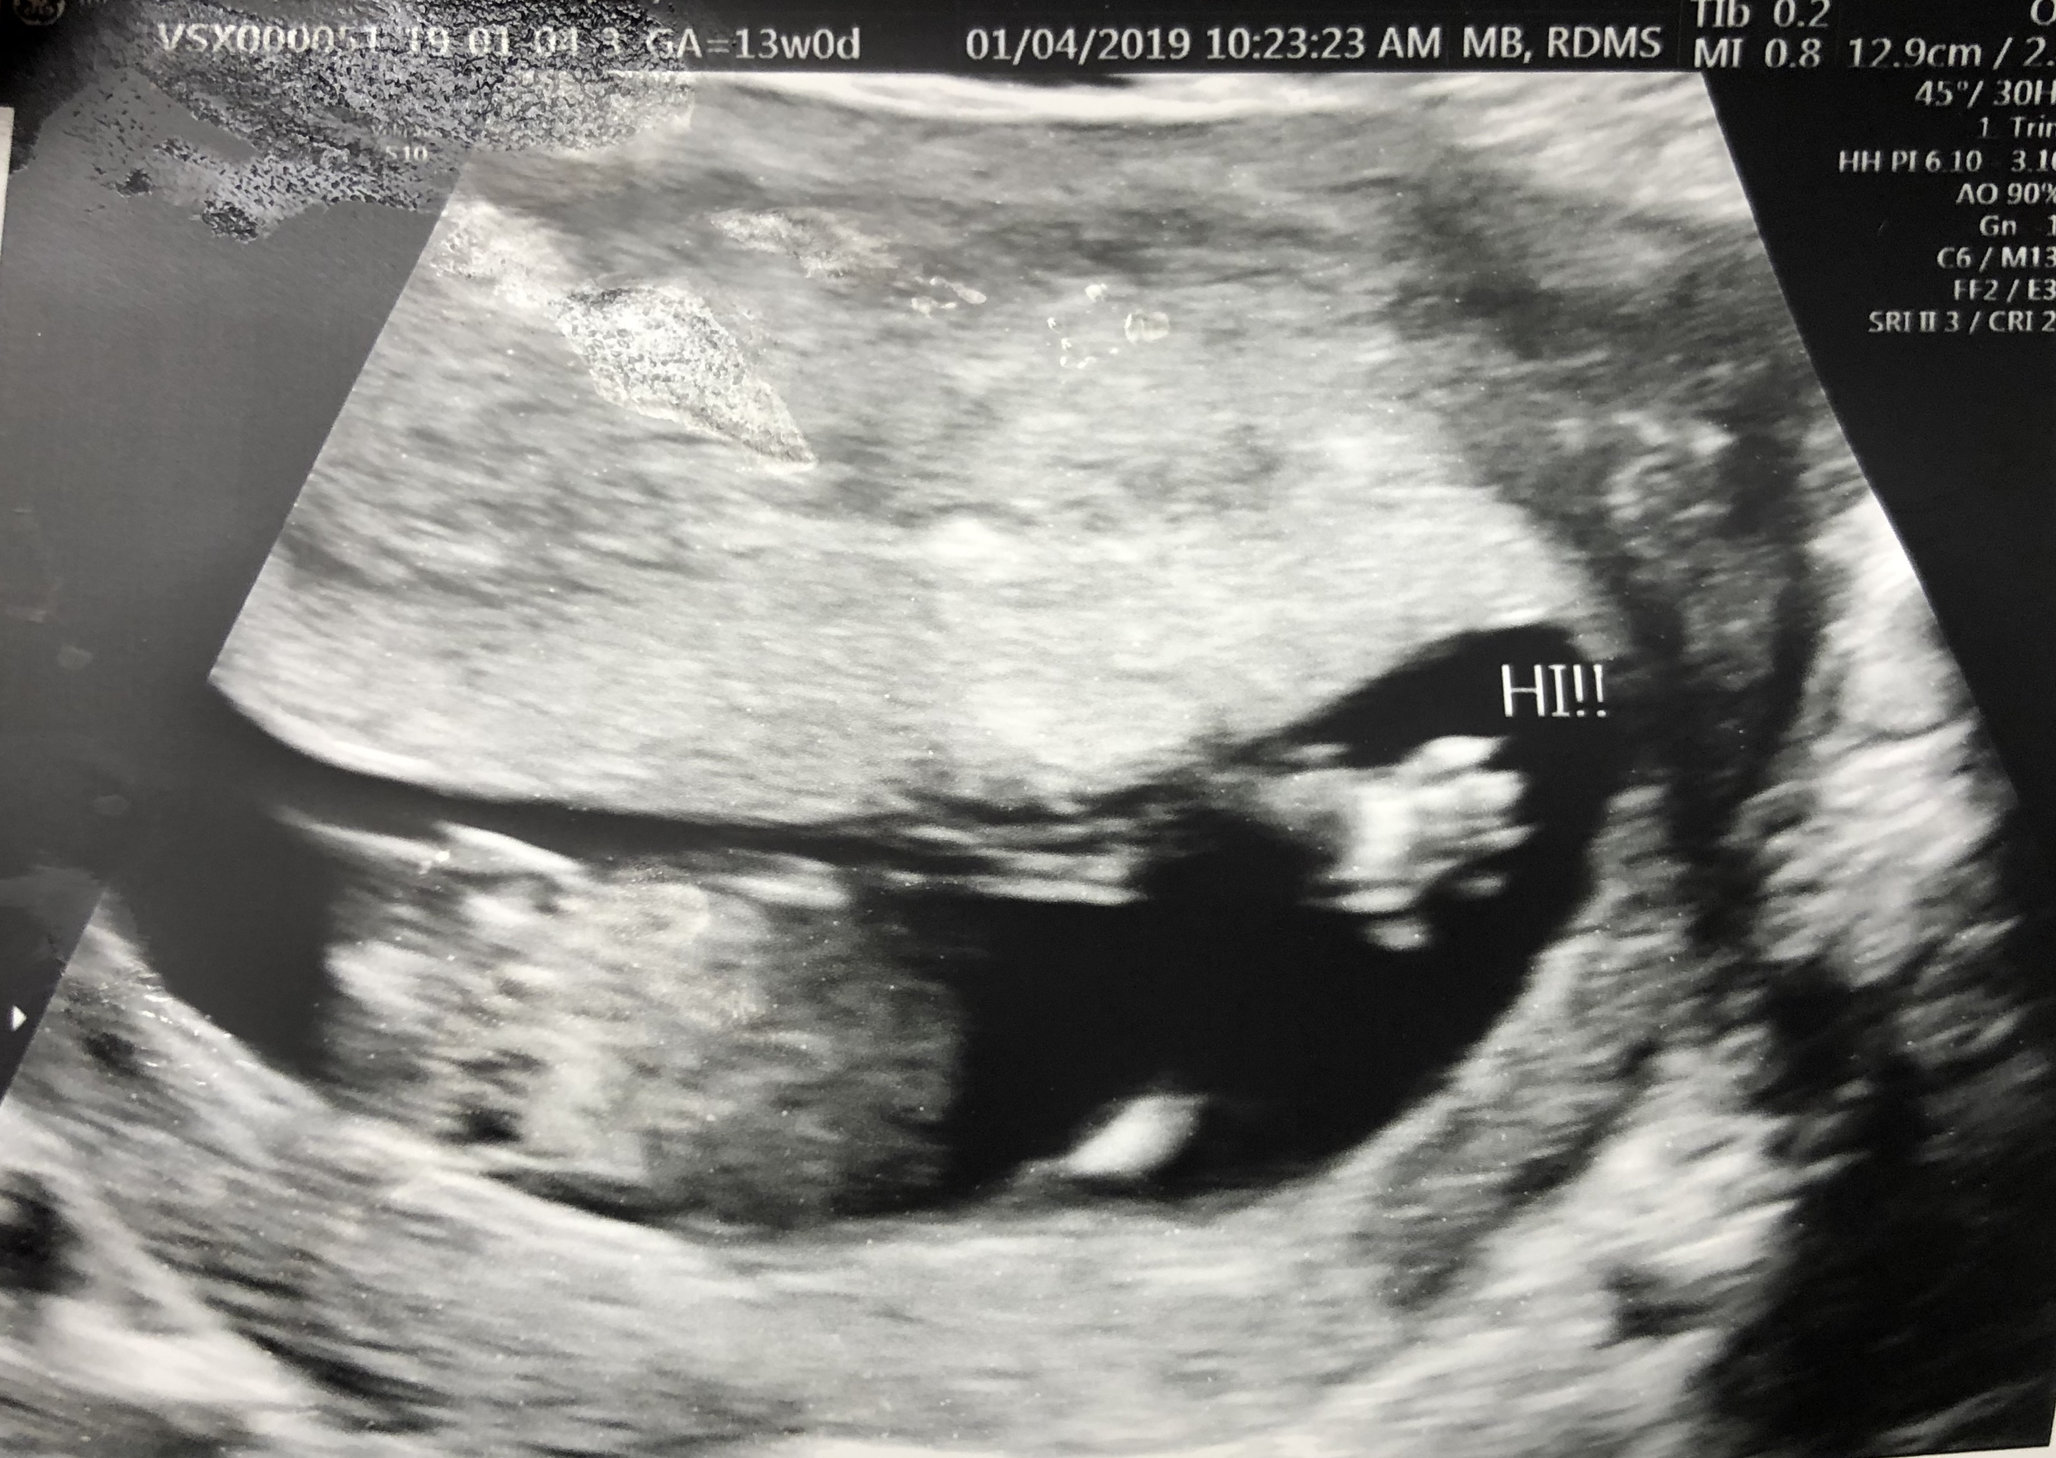

This pic was on Thursday at 13weeks2days. Can’t believe we are almost in our second trimester! She was moving around and bobbing her head. Love seeing her so active